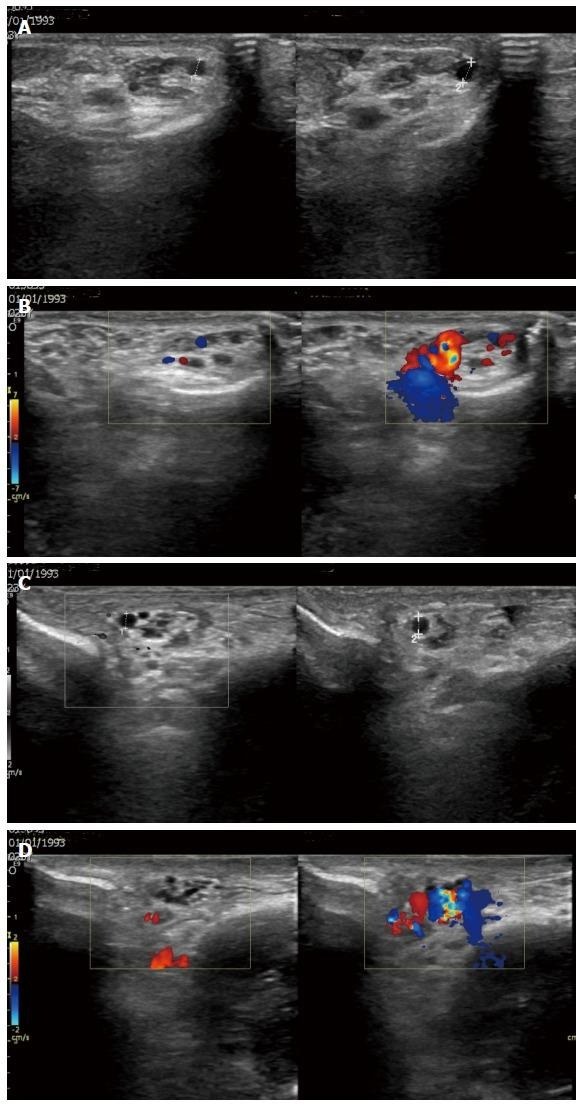

Pada USG Doppler, diagnosis varikokel ditegakkan jika ditemukan satu atau lebih vena dalam pleksus pampiniformis dengan diameter basal lebih dari 2.5 hingga 3 mm, yang menunjukkan peningkatan diameter dan adanya aliran darah balik (refluks) yang jelas selama manuver Valsalva.

Gambar 1. Pria 24 tahun dengan varikokel bilateral